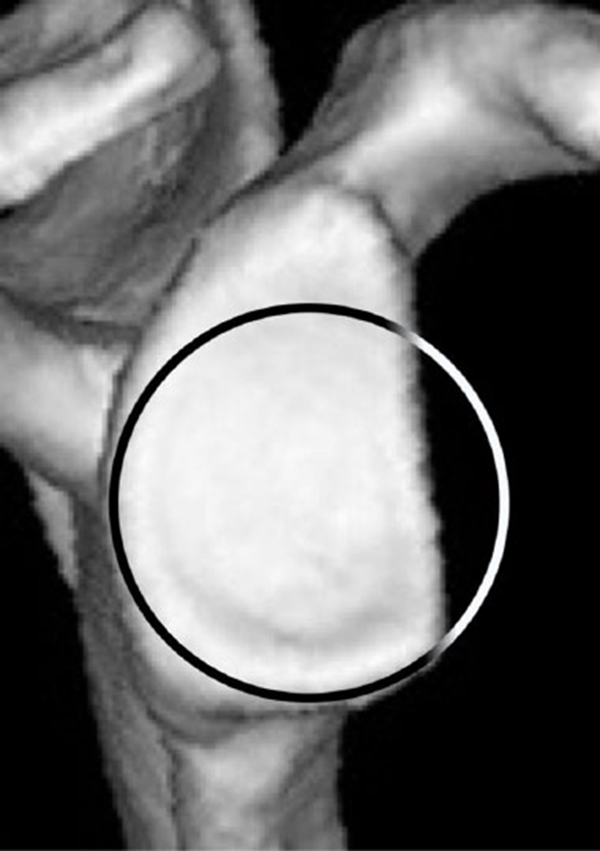

目前评估关节盂骨缺损的方法很多,如X线片、CT、3DCT、MRI和关节镜。使用3DCT的“en face”切面法是最被认可,因为它提供了对关节盂骨缺损最准确的评估。

①“最佳拟合圆”法。应用了一个最适合的圆圈,它完美地适合于关节盂的后部和下部。这个圆圈被认为接近关节盂的原始形状。